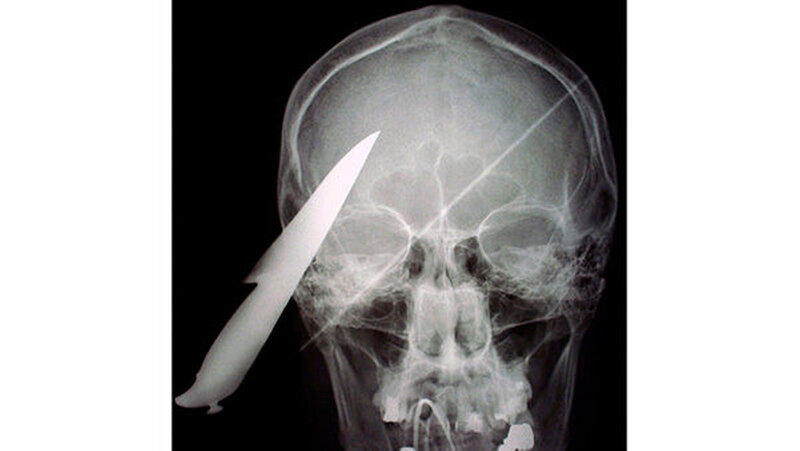

Fremdkörper im Gesicht

Vom Bohrer im Kopf bis zum Schlüssel in der Kieferhöhle: Die MKG-Chirurgen der Charité haben ausgewählte Patientenfälle mit Fremdkörpern im Gesicht zusammengestellt. In unserer Fotostrecke finden Sie die eindrucksvollen Aufnahmen.